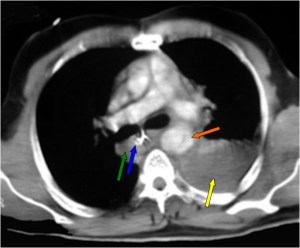

En el corte de TC con contraste vemos la sonda desplazada a la derecha de la línea media (flecha azul), un hematoma mediastínico (flecha verde) provocado por la rotura aórtica (flecha naranja), y un hemotórax izquierdo (flecha amarilla).